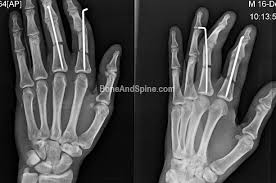

Phalanx Fractures Of Hand The Broken Fingers Bone And Spine